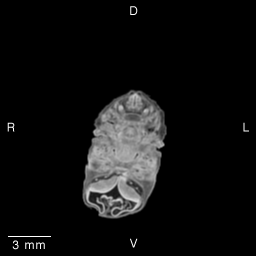

Stage 19 (Day 47), transverse slice 13